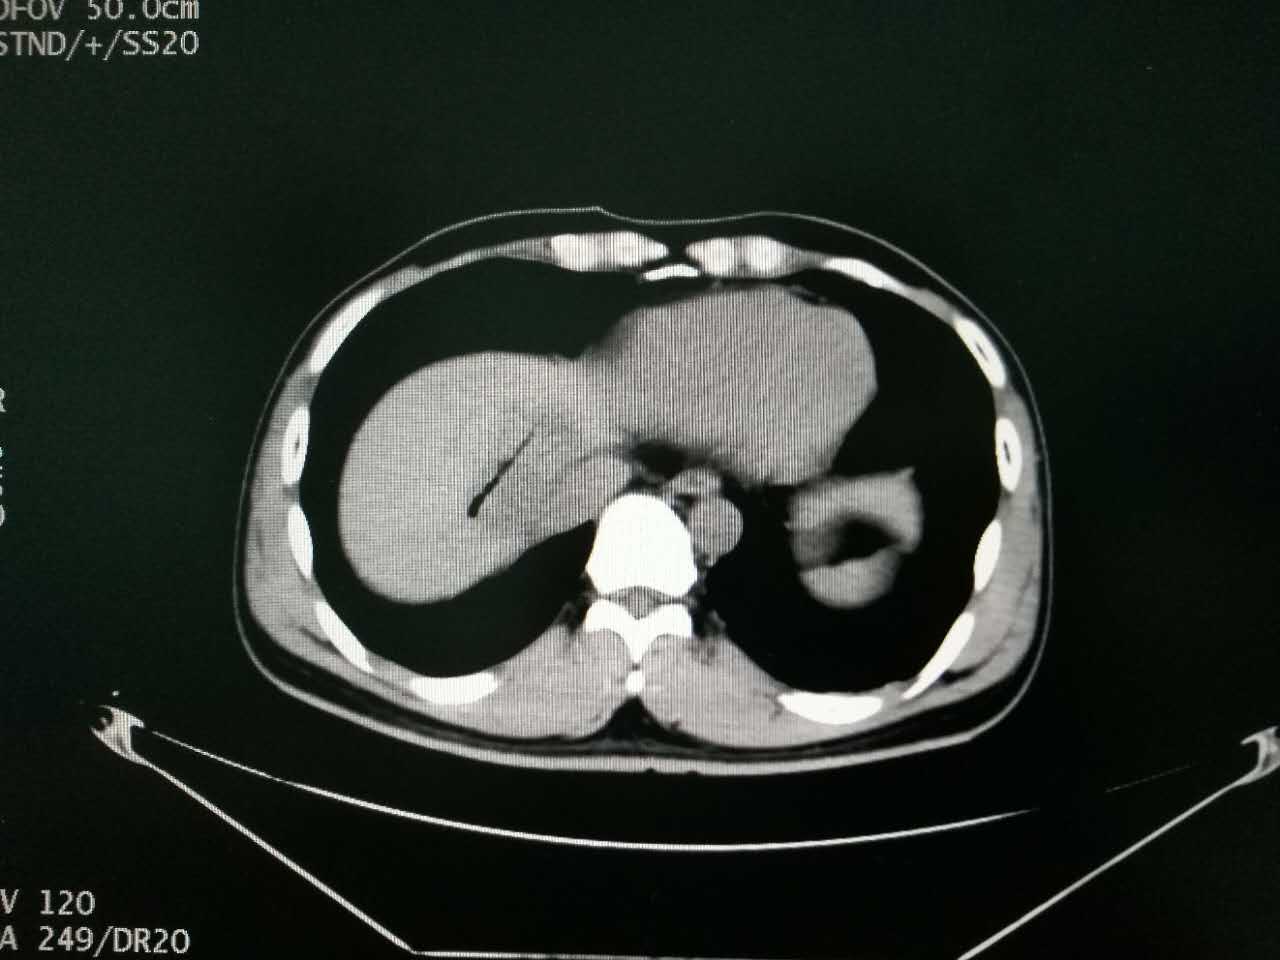

▲術(shù)后CT掃描見腫瘤消融完全